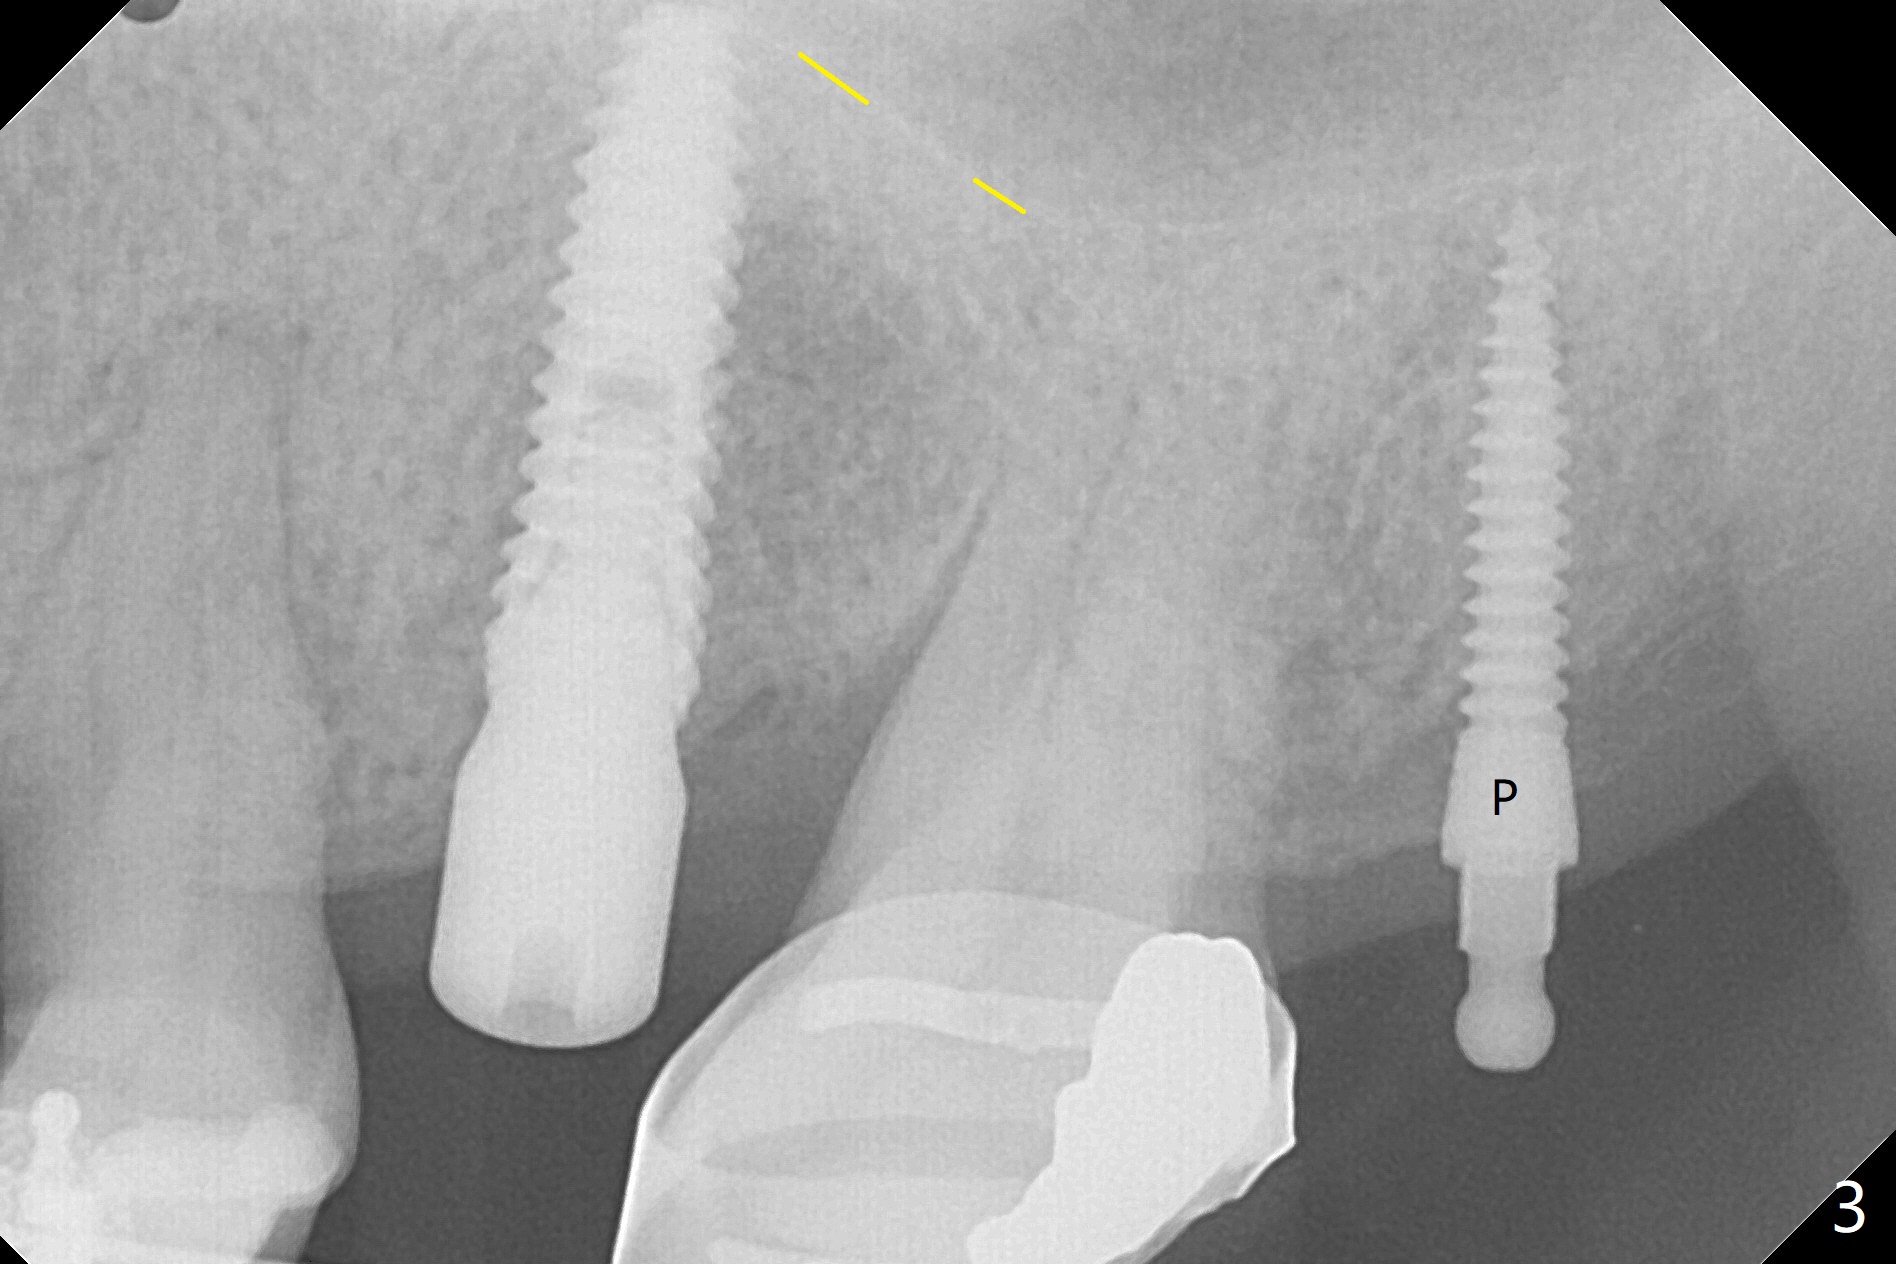

Eight-month limited ortho including use of a 1-piece implant (Fig.3 P (ball type)) as a distal anchor increases the mesiodistal space of #14 from <4 mm to 6 mm (near premolar width).  Guided surgery is not indicated because of presence of brackets and band and the narrow space.  Also due to the latter, incision is difficult to make.  In stead a 3.5 mm tissue punch is applied.  After 2.2 mm drill, a parallel pin is placed; it appears that the initial osteotomy is palatal (Fig.1).  Lindamann bur is adopted to move the osteotomy buccal.  The last drill (3 mm for 3.5 mm implant) has no resistance when it enters the buccalized osteotomy.  A longer implant than designed is placed (3.5x13 mm, Fig.2,3, close to the sinus floor (dashed yellow line) with 50 Ncm.  When the implant osteointegrates, it will be used a mesial anchor to distalize the 2nd molar.